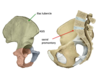

Identify these structures

The external sphincter of the stomach comes from where?

The right crus of the diaphragm. Function: sphincter that prevents stomach contents from refluxing up the esophagus when intra-abdominal pressure rises during inspiration